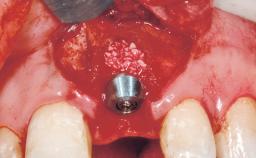

Late Flapless Placement of an Implant in a Maxillary Left Central Incisor Site

A 39-year-old male patient presented with a chief complaint of discomfort and gingival discoloration around his maxillary left central incisor. He was in good general health and was a non-smoker. His past dental history was significant because of the traumatic fracture of tooth 21 in a sporting accident at age 13. Initial dental treatment included endodontic therapy and a full-coverage restoration. The patient became symptomatic 5 years later, when structural failure of the tooth resulted in the dislodgment of the crown. Endodontic retreatment, apical surgery, and post-and-core restoration were performed.

Type of Implants One-Piece

Bone Augmentation Horizontal|Staged

Bone Volume Deficient horizontally, requiring prior grafting